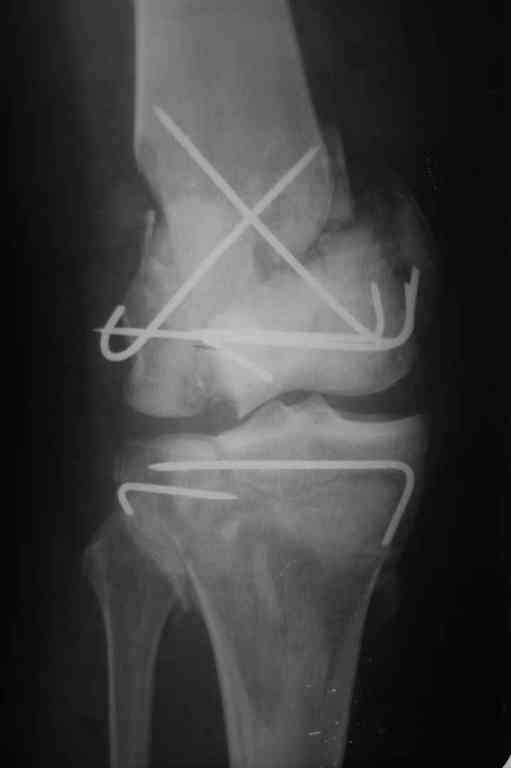

Здесь применение материала Plexur http://www.plexur.com для пластики при дефектах кости у больной с огнестрельной раной латерального тибиал плато с повреждением малоберцового нерва. Несмотря на интактный медиальный мышелок, для профилактики от вальгуса установлен АВФ и сделана ангиограмма.

После нескольких обработок и вакуумирования, поэтапно сделана фиксация тибиального бугра шурупами. И окончательную фиксацию закончили латеральной пластиной для тибиал плато и установкой пластического материала.

Для закрытия мягкотканых дефектов привлечена другая служба.